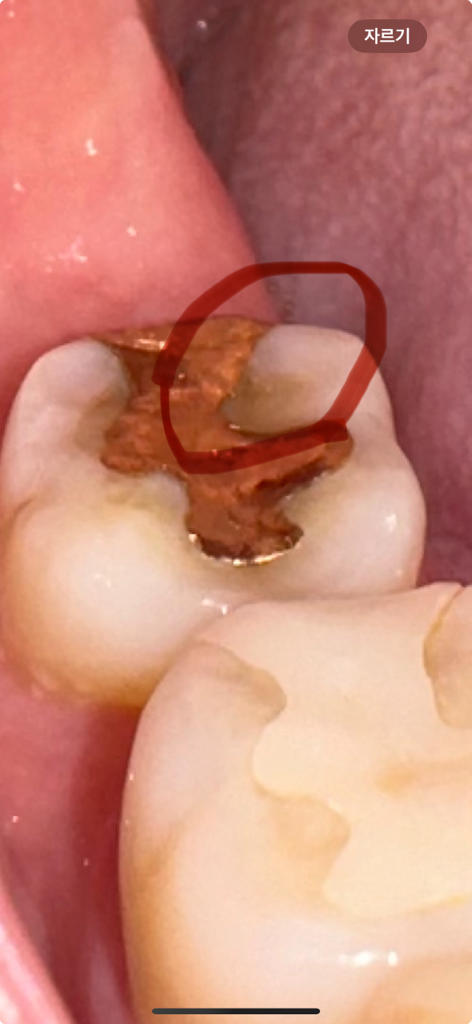

보철물 치아 다듬었는데 시려요 ㅠㅠ

저 부분에 음식이 끼여서 치과에서 보철물과 치아 둘 다 다듬어주셨어요 근데 다듬을때 너무 시리고 아팠는데 한 3일정도 계속 그래서 다시 갔더니 큰 이상 없다고 약 발라주셨어요 그러고나서 괜찮아졌는데 일주일 지난 지금 그 전보다 더 많이 시리고 아파요.. 이런 경우도 있나요? ㅠㅠ 바람 불어도 시리고 음식 씹을때도 시려요 ㅠㅠ 가만 있을때는 괜찮아요 다듬기전에는 하나도 안아팠는데 다듬고나니 너무 아프네요 금을 다듬은거라 그럴수도 있다고 하시는데 정말 아무이상 없는걸까요?

금속이 치과 재료중 열 전도율이 높긴하나 그와는 별개의 문제로 이차충치가 있거나 크랙이 있어서 그런 증상을 보일 확률이 높습니다 일반적으론 단순 교합조정으로 치아가 시려지거나 하진 않습니다

해당부위가 시린증상이 있는 경우 원인으로 크랙, 마모,충치, 잇몸염증등의 원인이 있기에 시린증상지속시에는 다시 치과 진료를 받길 권합니다.

만약 통증이 너무 불편한 경우에는 신경 치료 및 크라운 치료가 필요로 될수 있습니다.